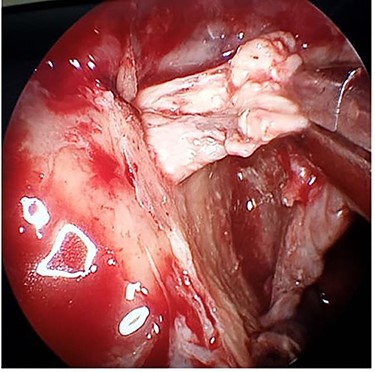

After multidisciplinary discussion, he was taken to the theatre the following day where he underwent right ethmoidectomy, uncinectomy and wide middle meatal antrostomy. The right sphenopalatine artery was found thrombosed (Fig. 4). This was combined with transoral resection of the right palatine process of maxilla. A sample of the discharge was sent for bacteriologic and fungal smear and culture. Immediate palatal reconstruction was performed using a temporary obturator which was replaced 2 weeks later by a permanent one. The smear was negative for both bacterial and fungal elements, and no growth was reported in the culture. The patient’s general condition improved and was discharged 4 days later.

Intraoperative endoscopic image of the thrombosed right sphenopalatine artery.